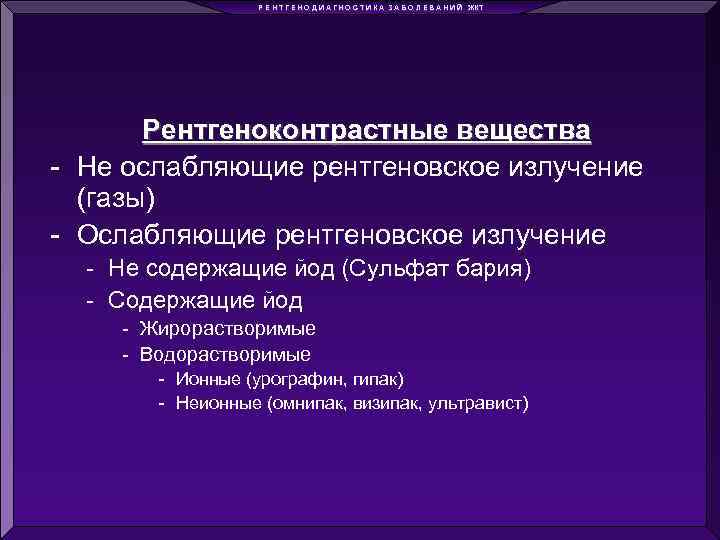

Р Е Н Т Г Е Н О Д И А Г Н О С Т И К А З А Б О Л Е В А Н И Й ЖКТ Рентгеноконтрастные вещества - Не ослабляющие рентгеновское излучение (газы) - Ослабляющие рентгеновское излучение - Не содержащие йод (Сульфат бария) - Содержащие йод - Жирорастворимые - Водорастворимые - Ионные (урографин, гипак) - Неионные (омнипак, визипак, ультравист)

Р Е Н Т Г Е Н О Д И А Г Н О С Т И К А З А Б О Л Е В А Н И Й ЖКТ Рентгеноконтрастные вещества - Не ослабляющие рентгеновское излучение (газы) - Ослабляющие рентгеновское излучение - Не содержащие йод (Сульфат бария) - Содержащие йод - Жирорастворимые - Водорастворимые - Ионные (урографин, гипак) - Неионные (омнипак, визипак, ультравист)